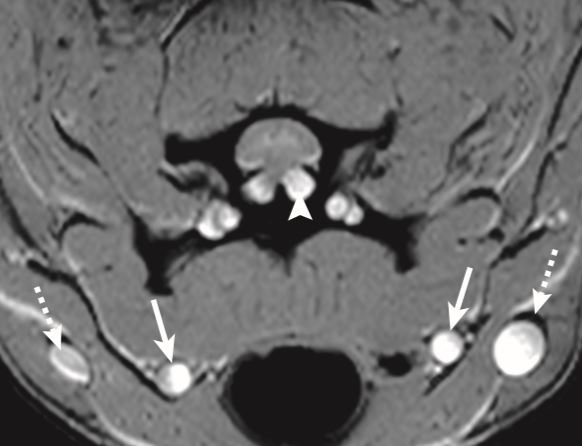

What is this artifact?

A

Flow related intravoxel dephasing

Why does flow-related intravoxel dephasing occur?

Different velocities of flow are present in the same voxel. So they have picked up different amounts of phase and there for likely cancel each other out. Causing reduction of signal